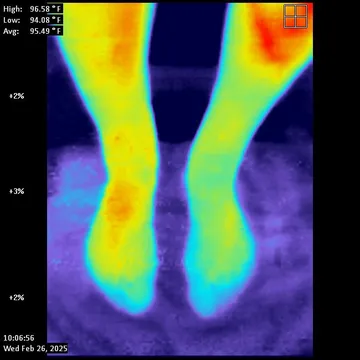

- Thermography used to monitor your response.  Non-invasive technology that shows your circulation as your care progresses.

Therm Hands                                    Therm Legs

Hand Thermography showing cold left hand                                    Foot Thermography showing poor circulation

MC Pre Thermal                                         MC Post

Before SoftWave:  Blue and Purple means poor circulation                                               6 weeks of SoftWave: Red indicates excellent circulation

In Office Case

A 75 year old male started care in July, 2024 for symptoms of lumbar spinal neuropathy.  He had the usual symptoms including pain, burning and

numbness in his legs and feet.  It also affected his balance which is very common due to the interference of nerve signals traveling from the feet and legs

to the brain.  Left untreated, this condition causes a slow death of tissue, nerves and blood vessels hence affecting the communication between the legs /

feet and the brain.  The before and after thermal images tell the story.

JC Pre Thermal                                      JC Thermal Post

Before SoftWave: Blue in the toes indicates poor circulation                    6 Weeks of SoftWave: Red indicates healthy, normal circulation